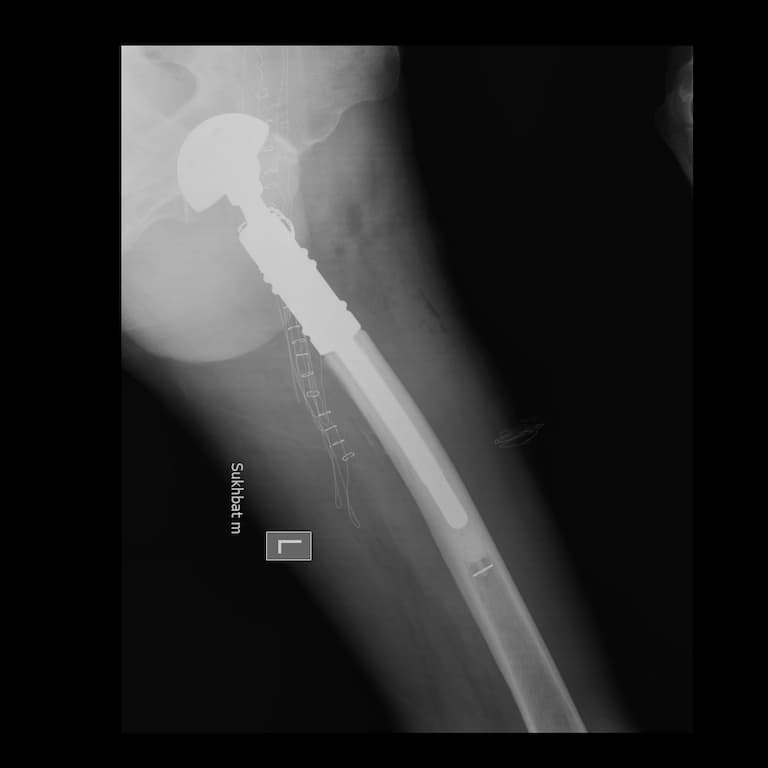

Дунд чөмөгний дээд хэсгийн /проксималь/ хавдар

Дунд чөмөгний проксималь буюу дээд хэсгийг хамарсан яс, зөөлөн эдийн гаралтай хавдрын улмаас түнхний үе, дунд чөмөгний дээд хэсгийг бүхлээр нь солих (мөч хадгалах мэс засал) мэс заслын эмчилгээг хийнэ.

Мэс заслын өмнөх болон дараах рентген зураг